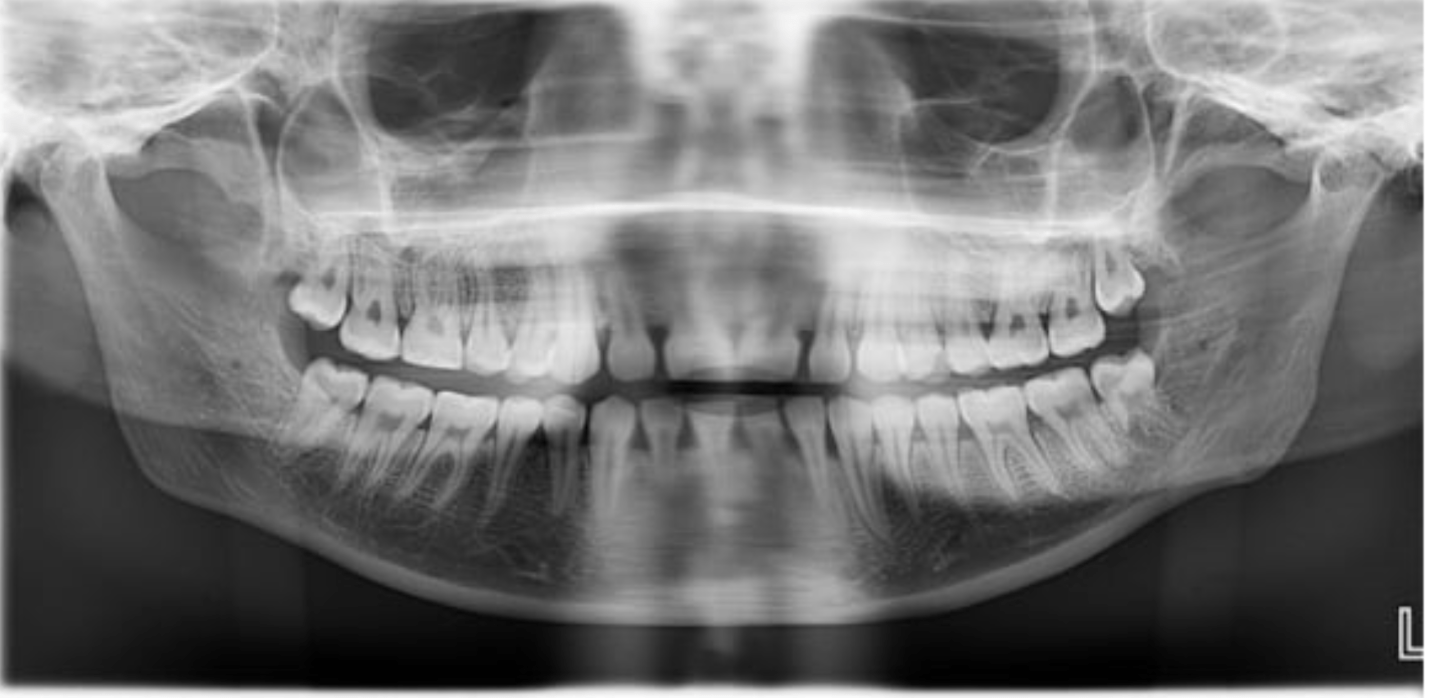

This caused the generalized blurriness in the image...

Patient movement